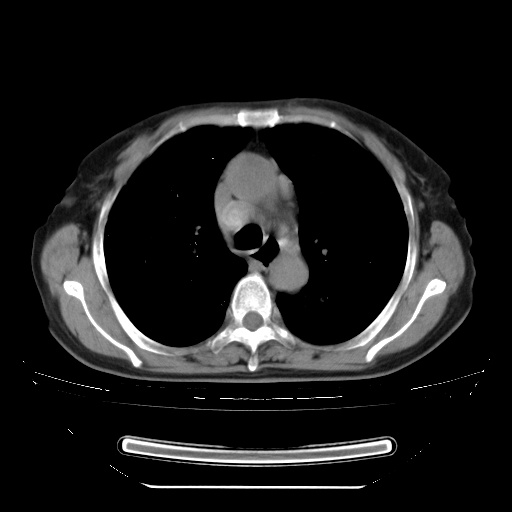

查原发灶吧,肺内转移瘤!肝内也有病灶,需强化明确。

以下是引用zsl6918在2009-3-5 23:00:00的发言:[br]查原发灶吧,肺内转移瘤!肝内也有病灶,需强化明确。

两肺内病灶呈小结节状和树芽状,纵膈的肿大的淋巴结密度不均匀,并见有钙化,考虑为两肺结核可能更大些。

两肺内病灶呈小结节状和树芽状,纵膈的肿大的淋巴结密度不均匀,并见有钙化,多形态病灶,考虑为两肺结核,肝内考虑小囊肿。

增殖性多发性病灶,大小不一,分布不均匀,发生于肺泡中,纵隔淋巴结肿大其内有钙化,诊断:细支气管肺泡癌,

片子很好,质量很高,两侧肺门淋巴结肿大并有钙化,两肺弥漫病灶,首先考虑tb并播散,但年龄大了呀(72岁)小细胞肺癌不能除外,如果是肺癌也没什么大的治疗了,建议正规抗结核治疗后复查

纵隔见肿大淋巴结并钙化,首先考虑结核,但感觉小结节像“挂果”征,分布位于支气管边缘,所以不排外肺泡癌,建议抗唠后复查吧?不然是癌的话,也不好治吧?化疗?

以下是引用zhw974247在2009-3-6 6:25:00的发言:[br]两肺内病灶呈小结节状和树芽状,纵膈的肿大的淋巴结密度不均匀,并见有钙化,多形态病灶,考虑为两肺结核,肝内考虑小囊肿。